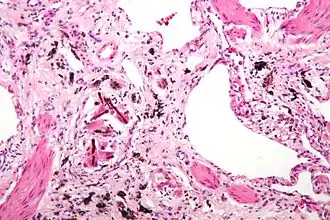

Пневмокониоз (лат. pneumon — лёгкие и konia — пыль) — группа заболеваний лёгких (необратимых и неизлечимых)[2], вызванных накоплением в лёгких достаточно большой дозы нерастворимой производственной пыли, вызывающей развитие в них фиброзного процесса[3]. Пневмокониозы относятся к профессиональным болезням. Начальные стадии не выявляются при флюорографии и могут быть обнаружены при вскрытии при вредном стаже менее 1 года[4]. Встречаются у рабочих горнорудной, угольной[5], машиностроительной и некоторых др. отраслей промышленности.

Пневмокониозы — хронические заболевания, обычно развивающиеся постепенно. Риск их развития зависит от накопленной дозы пыли, т.е. от соотношения между её поступлением, выведением, свойств пыли и длительностью работы в запылённых условиях. Течение заболевания зависит от условий труда (степень запылённости воздуха в рабочем помещении, состав пыли), наличия сопутствующих заболеваний (особенно органов дыхания, в том числе туберкулёза, и сердечно-сосудистой системы), индивидуальной чувствительности организма. Клинические проявления различны при разных видах пневмокониоза, хотя у них есть и общие признаки. В зависимости от степени выраженности фиброзного процесса различают несколько стадий заболевания. Вначале отмечаются боли в груди, сухой кашель. В дальнейшем появляются признаки лёгочной недостаточности, к которым затем могут присоединиться явления сердечной недостаточности. Нередко наблюдаются изменения (атрофия или гипертрофия) слизистых оболочек дыхательных путей, нарушаются функции желудка и поджелудочной железы, возникают нарушения обмена веществ. Осложнения: воспаление лёгких, туберкулёз, хронический бронхит, бронхоэктатическая болезнь.

Жалобы: непродуктивный кашель, прогрессирующая одышка. Развивается цирроз лёгкого, сморщивание лёгочной ткани с участками эмфиземы.

Наиболее часто он встречается у лошадей и собак. Лёгкие при этом приобретают диффузную или пёструю аспидно-черную или шиферную окраску. Значительное отложение угольной пыли вызывает воспалительные изменения, развитие соединительной ткани и индурацию лёгких[20].